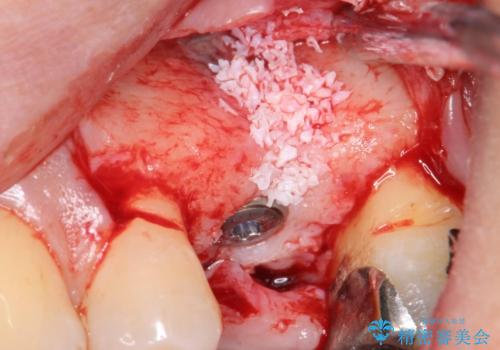

歯茎が腫れる インプラントでの治療

- 左上5/インプラント:242,000円 骨増生:55,000円 カスタムアバットメント:110,000円 インプラント用仮歯:22,000円 ジルコニアクラウン:121,000円 合計550,000円費用は治療当時の料金となります